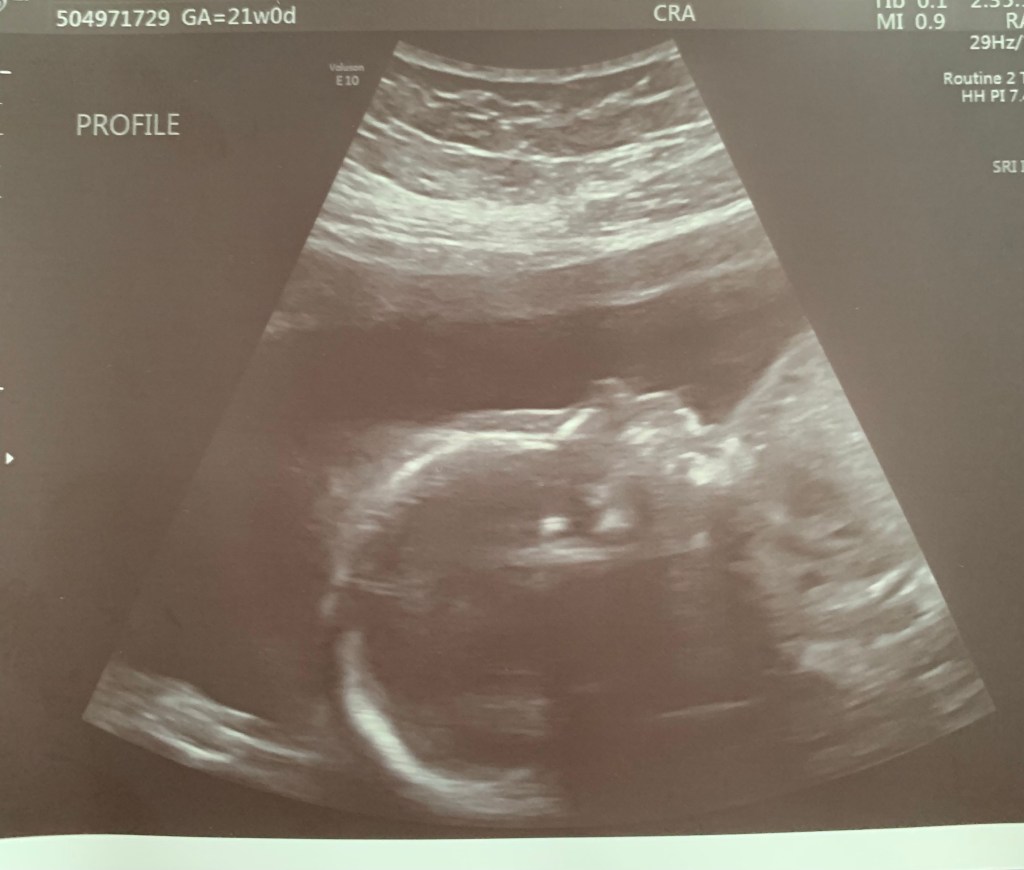

I was 21 weeks when we had our 20 week anatomy scan. It was so neat to see so many details of our baby as we hadn’t had an ultrasound since 8 weeks when baby looked like a little gummy bear! Everything looked great with baby’s development and he/she had a heart rate in the 150s and was just under a pound at 15oz putting them in the 70th percentile. Since we don’t want to know the gender, we had to close our eyes when the ultrasound technician got to the “between the legs part” of the scan. The funny part of the anatomy scan was that the ultrasound technician couldn’t get over our baby’s lips as apparently they have plump lips!